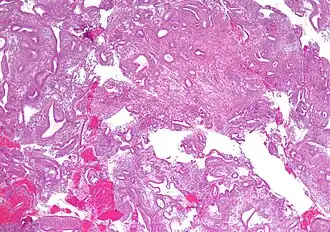

| Micrografia mostrando uma hiperplasia do endométrio, onde a proporção glândula-estroma está preservada, mas as glândulas apresentam um formato irregular e/ou estão dilatadas. Biópsia de endométrio. Coloração H&E. | |